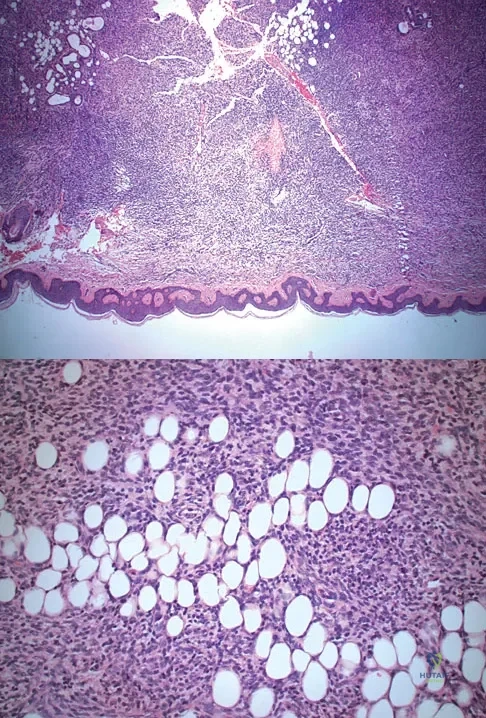

A 43-year-old woman is referred after excisional biopsy of a cutaneous soft-tissue mass from her left shoulder. Based on the biopsy specimens shown in Figures 44a and 44b, what is the best course of action?

A 16-year-old girl has had anterior leg pain and a mass for the past 8 months. Figures 2a and 2b show a radiograph and an H & E histologic specimen. Which of the following disorders is believed to be a precursor of this lesion?